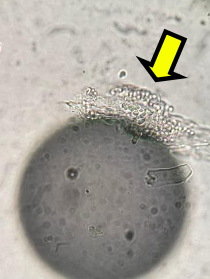

ウッド灯検査で光った毛を抜き、顕微鏡で観察したところ、写真の矢印で示すカビの分節 分生子が確認されました。